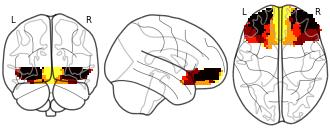

Connectivity-Based Parcellation of the Human Orbitofrontal Cortex: K=5...

EmailClick to copy linkLink copied Cite(2024). Connectivity-Based Parcellation of the Human Orbitofrontal Cortex: K=5 cluster map [Dataset]. http://identifiers.org/neurovault.image:887626niftiAvailable download formatsUnique identifierhttps://identifiers.org/neurovault.image:887626Dataset updatedNov 18, 2024License

Cite(2024). Connectivity-Based Parcellation of the Human Orbitofrontal Cortex: K=5 cluster map [Dataset]. http://identifiers.org/neurovault.image:887626niftiAvailable download formatsUnique identifierhttps://identifiers.org/neurovault.image:887626Dataset updatedNov 18, 2024LicenseCC0 1.0 Universal Public Domain Dedicationhttps://creativecommons.org/publicdomain/zero/1.0/

License information was derived automaticallyDescriptionK=5 cluster map based on N=13 participants.

Collection description

K-means cluster maps of orbitofrontal cortex with K=2, 3, 4, 5, 6, and 7 clusters based on resting-state fMRI data.